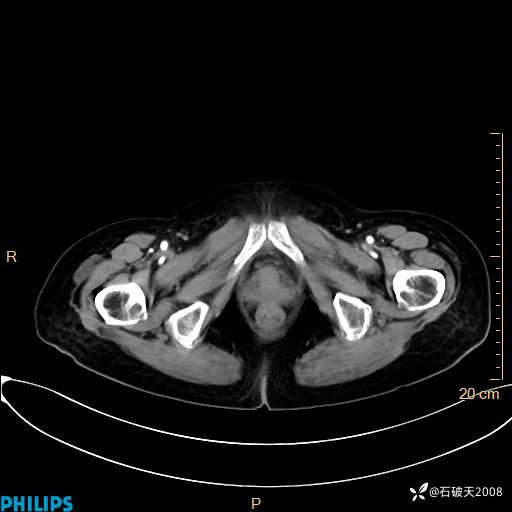

动脉期